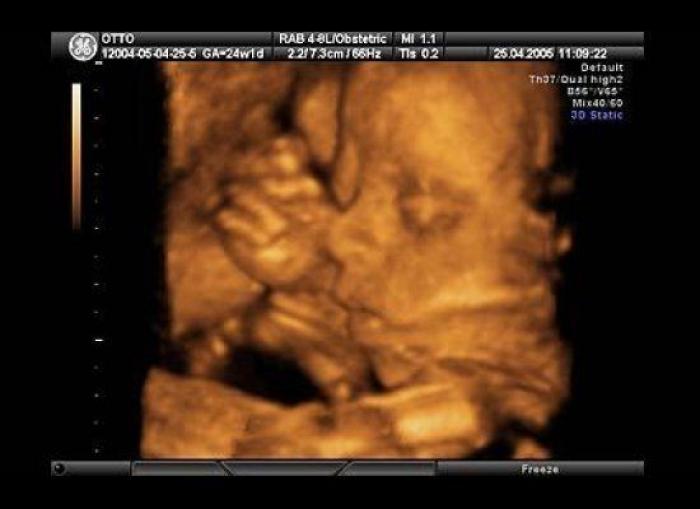

En esta galería puedes ver en fotos como es el desarrollo de un feto de semana en semana:

Desarrollo del feto, en fotos

Ver la galería